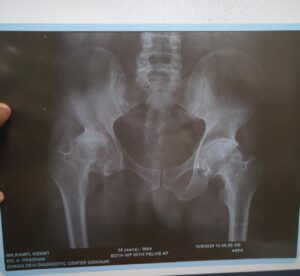

डॉ तरूण सिंह ठाकुर द्वारा मरीज की खून जांच की गई और एक्स-रे कराया गया। एक्स-रे में पाया गया कि मरीज के दायां कूल्हा पूरी तरह से खराब हो चुका था, जिसके लिए डॉ तरुण सिंह ठाकुर द्वारा कूल्हा प्रत्यारोपण की सलाह दी गई। मरीज के फिटनेस के बाद मरीज के दाएं कुल्हे का २ सितंबर को ऑपरेशन किया गया। मरीज का ऑपरेशन चुनौतीपूर्ण था, लेकिन ऑपरेशन के पश्चात मरीज पूरी तरह स्वस्थ है, दर्द मुक्त है और चलने फिरने में सक्षम है। ऑपरेशन टीम में प्रमुख डॉ तरूण सिंह ठाकुर (सहायक प्राध्यापक), डॉ प्रमोद जायसवाल, डॉ रवि महोबिया, डॉ सोमेश शुक्ला और पी जी रेसिडेंट शामिल थे। ऑपरेशन डॉ ए आए बेन (विभागाध्यक्ष अस्थिरोग) के मार्गदर्शन में हुआ। एनेस्थिसिया टीम में डॉ मधुमिता मूर्ति (विभागाध्यक्ष), डॉ मिल्टन, डॉ श्वेता, डॉ भावना और टीम शामिल थे। नर्सिंग में योगेश्वरी और टीम शामिल थे। एनेस्थिसिया डॉक्टरों का ऑपरेशन के पश्चात दर्द निवारण में विशेष योगदान रहा है। यह ऑपरेशन आयुष्मान कार्ड द्वारा निःशुल्क किया गया। इंपानेट उपलब्ध करने में डॉ आर मूर्ति (अधिष्ठाता) और डॉ लखन सिंह (चिकित्सा अधीक्षक) का विशेष योगदान रहा। यह ऑपरेशन डॉ आर मूर्ति (अधिष्ठाता), डॉ लखन सिंह (चिकित्सा अधीक्षक) विगत दो वषो में अब तक 35 कूल्हा प्रत्यारोपण एवं 25 घुटना प्रत्यारोपण आयुष्मान द्वारा निःशुल्क किया जा चुका है।